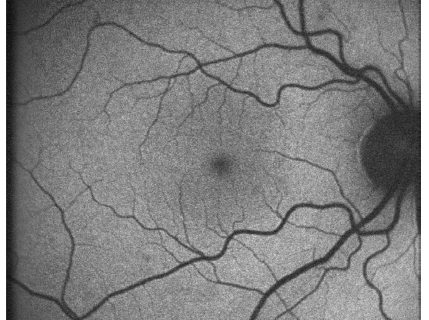

Αυτοφθορισμός

Στην τρίτη παρουσίαση της εκπαιδευτικής ενότητας: “Διαγνωστικές εξετάσεις – ερμηνεία και αξιολόγηση” συζητάμε τις βασικές αρχές και κλινικές εφαρμογές του αυτοφθορισμού του βυθού. Η σωστή κατανόηση των μεταβολικών, λειτουργικών και ανατομικών/δομικών παραγόντων που καθορίζουν την ένταση του σήματος φθορισμού μας βοηθά στην εύκολη ανάγνωση της διαγνωστικής αυτής απεικόνισης .